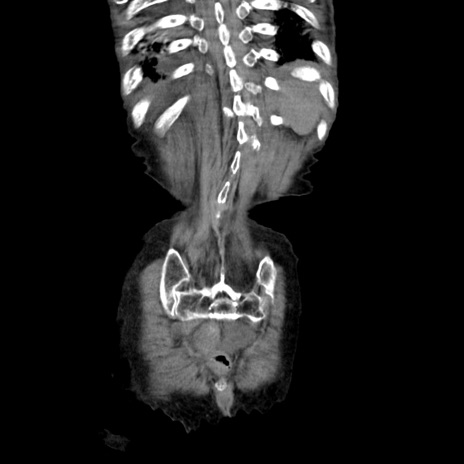

症例27(冠状断像)

【症例】80歳代女性

【主訴】嘔吐、腹痛

【現病歴】数時間前より嘔吐あり。心窩部痛出現し、徐々に右下腹痛あり。その後も数回嘔吐あり救急搬送となる。

【既往歴】左大腿骨頚部骨折手術

【身体所見】腹部は膨隆しているが軟らかく圧痛なし。腸雑音はやや亢進。

【データ】WBC 12000、CRP 19.05